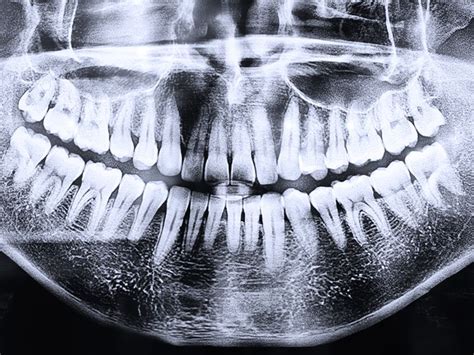

Radiografía panorámica dental mostrando diversas estructuras anatómicas.

La superposición del paladar duro con ensanchamientos orientados hacia caudal o con tabiques del receso alveolar en el sector posterior del maxilar puede simular la presencia de alteraciones quísticas. Del mismo modo, las superposiciones de los orificios nasales a la altura de las zonas apicales de los dientes 12 y 22 pueden dar al observador de una radiografía panorámica la impresión visual de una imagen radiolúcida apical. En este caso, la obtención de imágenes secuenciadas en otra proyección puede ser útil.

En procedimientos de imagen bidimensionales es frecuente que las dilataciones medulares del hueso esponjoso en el sector posteroinferior adopten una imagen de masa radiolúcida y sugieran al observador la existencia de un proceso patológico. Si dos radiografías diferentes no aportan información suficiente se debería utilizar una técnica de imagen tridimensional.